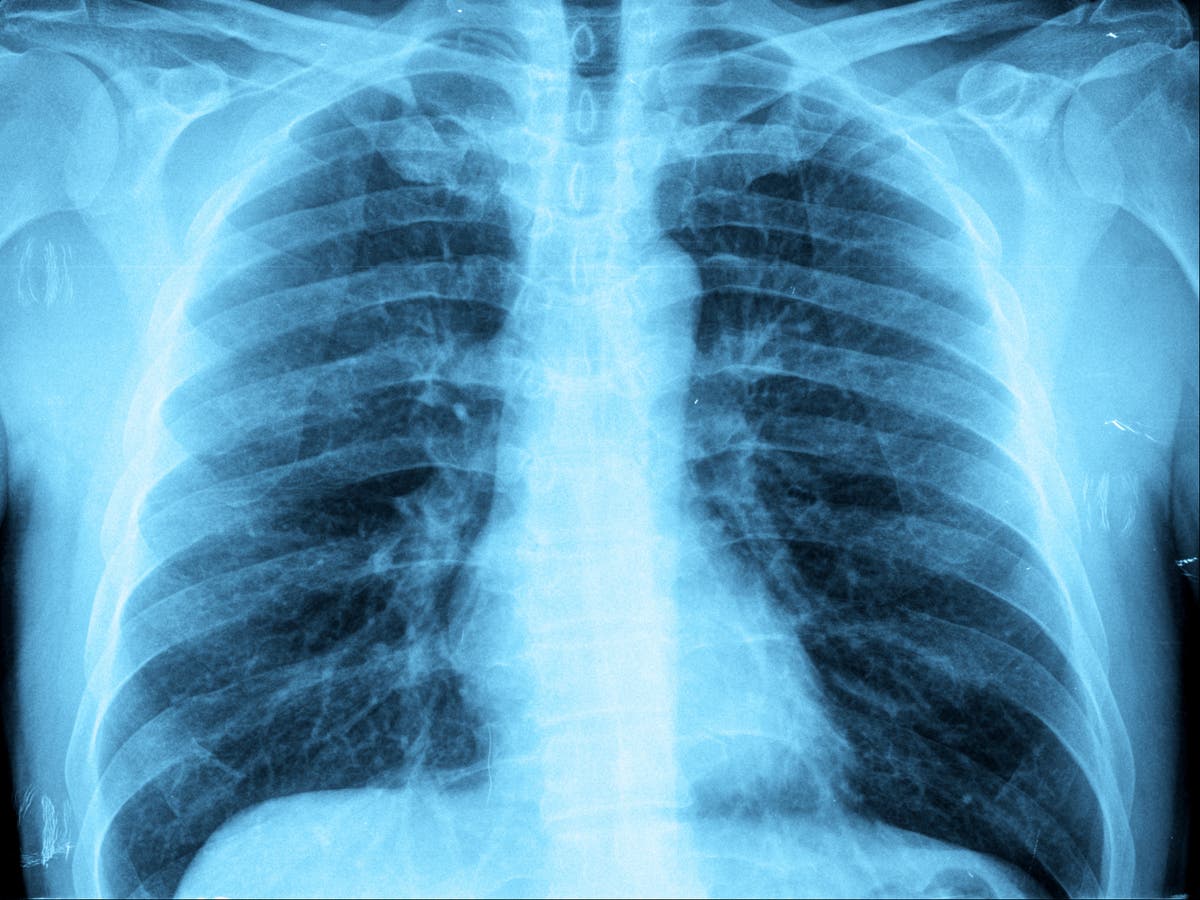

Health authorities in Ohio have reported a surge in pediatric pneumonia cases, with 145 cases reported since August. This outbreak, dubbed "white lung syndrome," is not linked to the pneumonia outbreak in China. The strains seen in Ohio are not spreading internationally. Medical experts believe the increase in cases is expected during the flu season and may be exacerbated by the lifting of COVID restrictions. The main pathogens detected in Ohio are streptococcus pneumonia, adenovirus, and mycoplasma pneumonia. Mycoplasma pneumonia, also known as "walking pneumonia," is a bacteria that causes mild infections and can be treated with antibiotics. The outbreak in Ohio is not considered severe, and most children are recovering at home. Health officials recommend getting updated COVID-19 and flu vaccines to protect against respiratory infections.